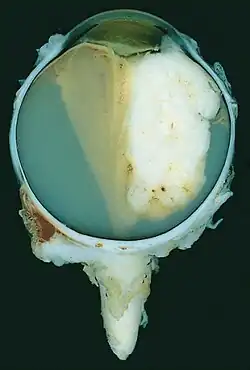

| A pathology specimen of a retinoblastoma tumor from an enucleated eye of a 3-year-old female | |